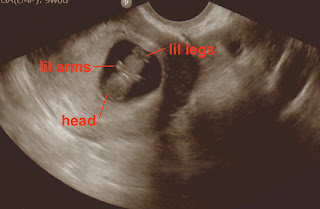

As for the baby's progress to date - he/she is about the size of an apple or pear - about 4"-5" long from crown to rump and weighs about 2.5-3 ounces. He/she is already moving amniotic fluid through the nose and upper respiratory tract, which helps the primitive air sacs in the lungs begin to develop. Baby's legs are growing longer than his/her arms now, and can move all those tiny joints and limbs! The eyelids are still fused shut, but he/she can sense light already and has taste buds forming! Baby can also hear sounds and voices. The bones are also growing and strengthening enough that he/she is able to work on straightening his or her neck and head even more. His/Her face is now complete with eyelashes and eyebrows! SO COOL!

This is our second ultrasound at 9 weeks - what a CRAZY difference 4 weeks can make! To me this one looks like Baby Barber is a precious little gummy bear with the tiny arms and legs ;)